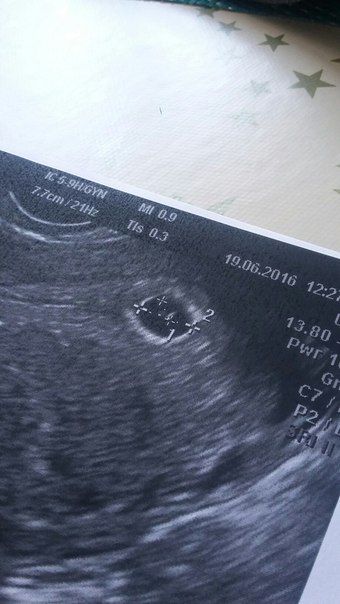

19.06.2016

С утра вроде нет выделений... А потом вроде пошли опять... Слизистые, но в прожилками кровяными... Муж как стена ходит, каждый час спрашивает что да как. Нервы сдают. Мы едем на узи, благо муж работает в роддоме. Малышка наша выросла за 1,5 суток ого-го как!

Плодное яйцо 7,8 мм, появился желточный мешочек, ура! Желтое тело около 17 мм. Сидит глубоко, высоко, все в порядке. Нашли небольшие остатки гематомки, успокоили, что все в порядке. Фух!!!!!!!!!! Вечером помыла два окна)))))